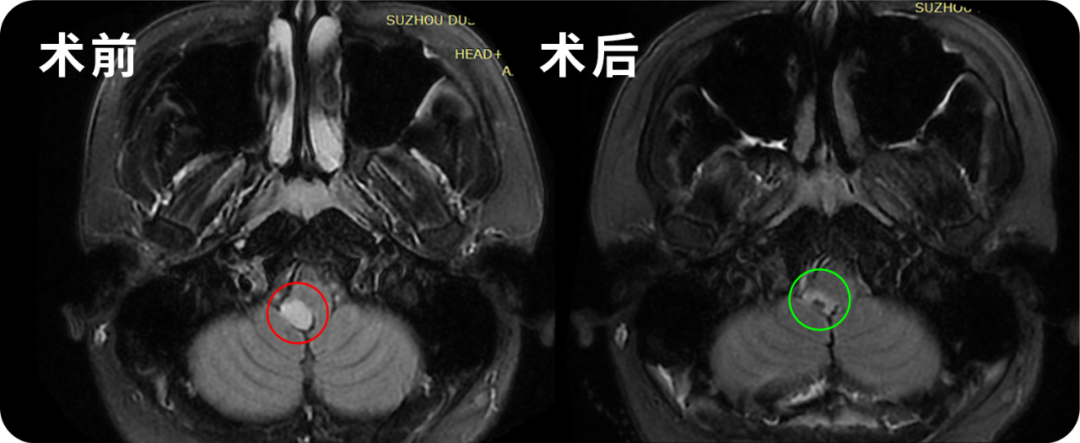

延髓胶质瘤真的就是不治之症吗?"无法手术、存活时间有限"——当39岁的陈先生偶然查出延髓胶质瘤时,他陷入了深深的绝望之中。他还如此年轻,拥有幸福的家庭,如果还有一线生机,他一定要尽全力抓住。幸运的是,他抓住了那根救命稻草,成功完成了手术。

24岁的川川也被查出脑干延髓胶质瘤,成功手术后生命体征平稳,四肢活动自如。而为他们实施手术的医生,都是INC巴特朗菲教授。

世界脑干手术领域权威专著《Brainstem Tumors》(脑干肿瘤)中,巴特朗菲教授撰写了《Surgical Approaches to Medullary Tumors》(延髓肿瘤的外科手术方法)章节,详细分享了从术前规划,到术中操作技巧的全套技术要点。

通过回顾相关文献可知,许多医生认为延髓胶质瘤无法手术。然而,通过合理的患者选择策略,即使对于复杂病变,显微外科肿瘤切除也是可行的,正如本章所展示的,手术有望达到良好预后,以及极低的并发症发生率。巴特朗菲教授深信手术在延髓胶质瘤的整体治疗中扮演重要角色。在现代分子诊断的背景下,肿瘤取样在不久的将来可能获得更多重要性。术中持续的电生理监测有助于指导术者进行尽可能多的肿瘤切除并避免手术并发症。外科医生在显微外科干预期间的灵活态度,例如不试图在缺乏与延髓实质清晰界限的弥漫性病变中追求理想的高肿瘤切除率,可能有助于避免对延髓的不可逆损伤。另一方面,至少在所有与脑干实质清晰可辨的局灶性低级别肿瘤中,应尝试根治性肿瘤切除,因为可能对患者的生存期和生活质量带来积极意义。当然,关于肿瘤究竟该切除多少,应始终在手术中根据局部情况和特定的肿瘤组织特性做出抉择。